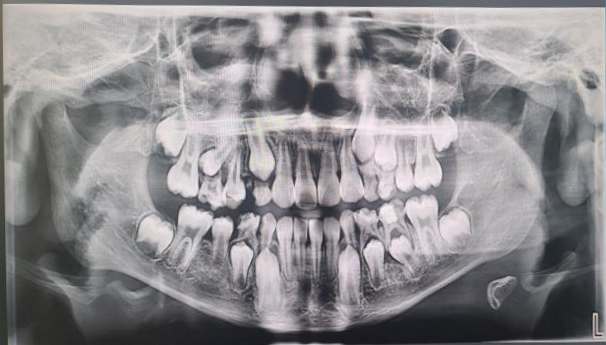

牙齿由于龋坏等原因而致使牙冠的大部分缺损,仅剩余牙根,称为残根。那这样的“烂牙根”能否放任自流不治不拔呢?答案是否定的。残根长期留在口腔有哪些隐患呢?下面马医生一一跟大家分享。

•残根的保留和拔除•

一般情况下,残根缺损到牙龈下不超过3mm,牙根有足够的长度,牙槽骨没有吸收,通常可以尝试保留做桩核冠修复或覆盖义齿等;如果残根缺损到牙龈下超过3mm,或磨牙已经破坏髓室底,通常建议及时拔除,及时修复。当然残根的处置医生还要结合患者的意愿来决定。残根保留治疗或者拔除镶牙都会花费更多的时间和费用,因此牙齿出现龋洞一定要尽早补起来,日常应认真仔细的刷牙,定期做口腔检查,维护口腔健康!